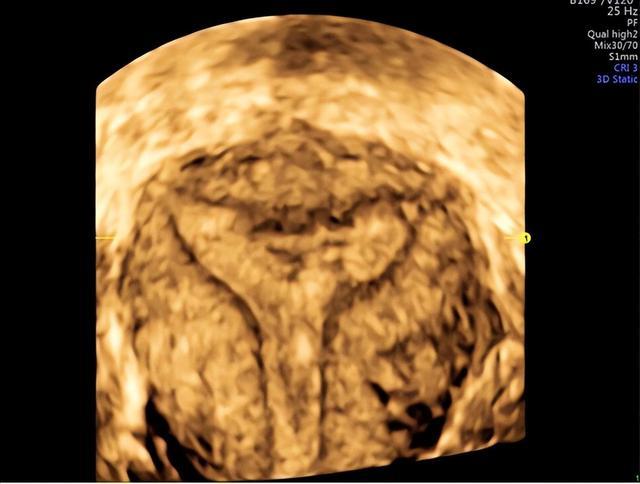

下图宫腔形态正常,但宫腔内有多处片状内膜缺失。

当宫腔形态失常时,我们可以看到中段内聚、缩窄,宫腔内凹凸不平。